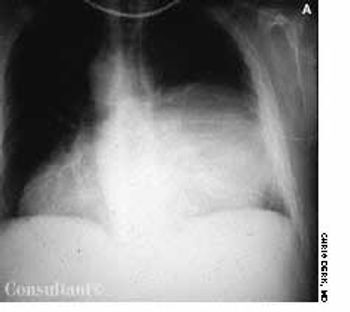

Shortness of breath and cough were the sole complaints of a 49-year-old man who had no significant medical history. He was given antibiotics for a possible bronchitis. The patient returned a week later because his symptoms had not improved. At this time, a chest film showed a right-sided mediastinal mass, and a CT scan of the thorax located the mass in the posterior mediastinum.